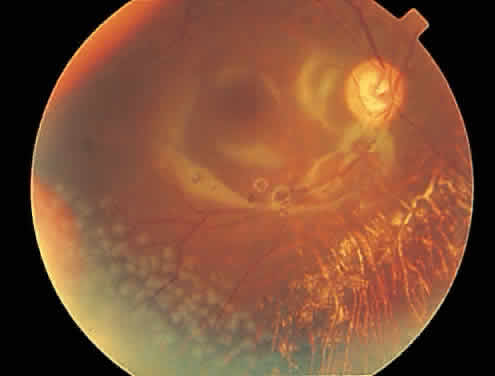

mild anterior uveitis is extremely unusual with AIDS-associated CMV retinitis. The hallmark lesion of CMV retinitis is a necrotizing, full-thickness retinitis that results in retinal cell destruction. CMV often initially affects retinal tissue adjacent to major retinal blood vessels or the optic disc (Fig. 1). This is consistent with the concept that the virus is spread to the retina hematogenously. In most cases, the pattern of infection is classic and distinctive, making clinical diagnosis straightforward. The area of active retinitis has a granular, dirty-white appearance. As the virus attacks the endothelial cells of blood vessels, hemorrhage is common. Advancement in the retinitis by both direct cell-to-cell transmission as well as spread by way of adjacent satellite lesions can be seen. Except for cases in which retinitis is acute, it is common to see areas of healed retinitis beside areas of active necrosis. Areas of burned-out necrosis show absence of any retinal tissue, whereas the underlying retinal pigment epithelium assumes a “salt and pepper” appearance. CMV retinitis can present initially as either large areas of retinal necrosis with hemorrhage or one or more small, focal areas of retinal whitening.1,12,14 These small, focal lesions may on occasion be confused with cotton-wool spots or lesions of toxoplasmosis.5,27 Unlike cotton-wool spots, focal areas of CMV may appear outside the posterior pole. These early, focal infiltrates of CMV may not be associated with retinal hemorrhages or vitreous cells. Over a course that usually spans weeks, infiltrates of CMV tend to assume two different patterns of clinical disease.11,12 The first pattern is called hemorrhagic and is characterized by broad geographic zones of retinal whitening. These large, geographic lesions are usually in close proximity to a major retinal blood vessel or the optic nerve. Satellite lesions are common. When the retinal necrosis associated with CMV retinitis becomes widespread, it is almost invariably associated with retinal hemorrhages. Although the border between necrotic and unaffected retina is sharply demarcated, the border itself appears irregular and jagged. Exudation into the retina or subretinal space may be seen, adding to the granular appearance of the retinitis. Juxtaposition of large zones of white, granular necrosis with those of red retinal hemorrhage has led this appearance of CMV retinitis to be described as either “pizza-pie” or “cheese and ketchup.” The retinal blood vessels, both arteries and veins, in the areas of necrosis commonly appear sheathed, secondary to a vasculitis. As a consequence, secondary retinal vascular occlusions, especially branch retinal vein obstructions, may occur in the course of CMV retinitis. Immune-mediated vascular damage may play a role in the vasculitis.12 Central healing of these lesions will occur as the infection progresses. Avasculitis resembling “frosted branch angiitis” hasbeen reported (Fig. 2).28 A second pattern of CMVretinitis has been labeled “granular” or “brushfireborder.” In this appearance, the focal granular infiltrates enlarge slowly across a line, leaving ever-increasing areas of destroyed retina and atrophic retinal pigment epithelium behind. Hemorrhages and vitreous cells are a less prominent feature. There appears to be direct cell-to-cell transfer of infected virions in this pattern of infection (Figs. 3 and 4). The brushfire border is commonly seen in CMV retinitis lesions anterior to the equator (Fig. 5). The significance, if any, of these two clinical patterns of CMV retinitis is not known, and, in some eyes, both patterns of disease can be seen simultaneously or in sequence. Progression of retinitis has been defined in clinical trials as movement of a lesion border at least 750 μm along a front that is 750 μm or more in length, development of a new CMV lesion in a previously involved eye or in the uninvolved fellow eye of a patient with baseline unilateral disease.29 Without treatment or improvement in the host's immune system, CMV retinitis is a relentless, slowly progressive infection resulting in blindness caused by total retinal necrosis, retinal detachment, or optic nerve involvement, in any combination.

CMV infection can affect the optic nerve either directly or by extension from adjacent retinitis (see Fig. 2).30–32 When direct involvement occurs, optic neuritis with profound, irreversible visual loss usually develops. Several cases of CMV optic neuritis associated with adjacent retinitis have been treated successfully. Exudative retinal detachment can occur during the course of CMV retinitis as well.4,12,30 The subretinal fluid is seen primarily inferiorly in the fundus and shifts with position. No retinal break will be evident; however, in areas of extremely thin, atrophic retina, it can be quite difficult to determine whether a full-thickness defect is present. Exudative retinal detachment associated with CMV is usually nonprogressive and may respond to ganciclovir therapy. Other features may include a mild to moderate anterior chamber cell and flare reaction. A hypopyon has rarely been reported in a renal transplant patient.4 Although mild vitreous cells are almost universally present, a florid vitritis severe enough to result in media opacity rarely develops from isolated CMV retinitis. In one patient who was immunosuppressed as a result of systemic corticosteroid therapy, a severe panuveitis associated with CMV retinitis was reported.32 More recently, an entity called immune recovery retinitis has been described.26,27 Immune-recovery uveitis is a chronic inflammatory syndrome associated with clinical immune reconstitution in AIDS patients with CMV retinitis who are taking HAART.33–35 It has emerged as an important cause of visual morbidity. Although immune recovery associated with HAART has allowed some patients to discontinue specific anti-CMV therapy, the rejuvenated immune response can be associated with this sight-threatening inflammation in some patients with preexisting CMV retinitis. Ocular features of immune-recovery uveitis include a significant vitritis that is more pronounced than that occurring with primary CMV retinitis. Additional features may include optic disc and macular edema. The mean CD4+ T-lymphocyte count in one study was 393 cells/mm3 at the time of diagnosis.33 Long-term vision-threatening complications related to this persistent inflammation include proliferative vitreoretinopathy, epiretinal membrane formation, posterior subcapsular cataracts, and severe postoperative inflammation.36 Rhegmatogenous retinal detachment occurs in 10% to 20% of eyes with CMV retinitis.37–39 However, before the AIDS epidemic, there were only five reported cases of this association.10,40 In patients living more than 1 year with CMV retinitis, risk of retinal detachment may be as high as 50%,41 which increases if more than 25% of peripheral retina is involved by disease.41,42 Retinal breaks in eyes with CMV retinitis typically occur within or at the border of necrotic atrophic retina (Fig. 6).43 The ensuing retinal detachments are typically difficult to repair with standard scleral buckling procedures. This is because of the location and number of retinal breaks, the difficulty in visualizing all breaks in necrotic retina, and the high incidence of associated proliferative vitreoretinopathy. In many cases, pars plana vitrectomy and retinal tamponade with silicone oil or long-acting intraocular gas is indicated (Figs. 7 and 8).37,44,45 However, scleral buckling may be considered in small peripheral retinal detachments when the entire involved area can be completely placed on the element. Laser photocoagulation demarcation has also been described to delimit macula-sparing CMV-related retinal detachment.46 Although anatomic success of macular reattachment with surgery is high, the visual results are often limited by the underlying disease process.47 When considering surgical repair of CMV-induced retinal detachment, consideration should be given to the potential for ambulatory vision, the patient's systemic condition and the status of the fellow eye.